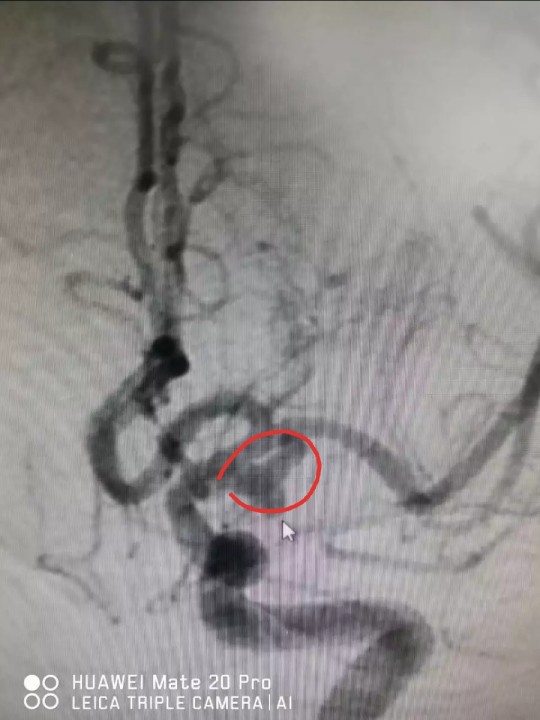

5月17日,瑞医神经外科手术团队为郑女士开展了双微导管下的脑动脉瘤栓塞术。该手术是将两根微导管同时置放于动脉瘤腔内,再用交互编织的弹簧圈进行栓塞。2个小时的术程,颅内“炸弹”被成功拆除,重要小分支血管保护完好,血流通畅。

术后CTA显示颅内动脉瘤已栓塞